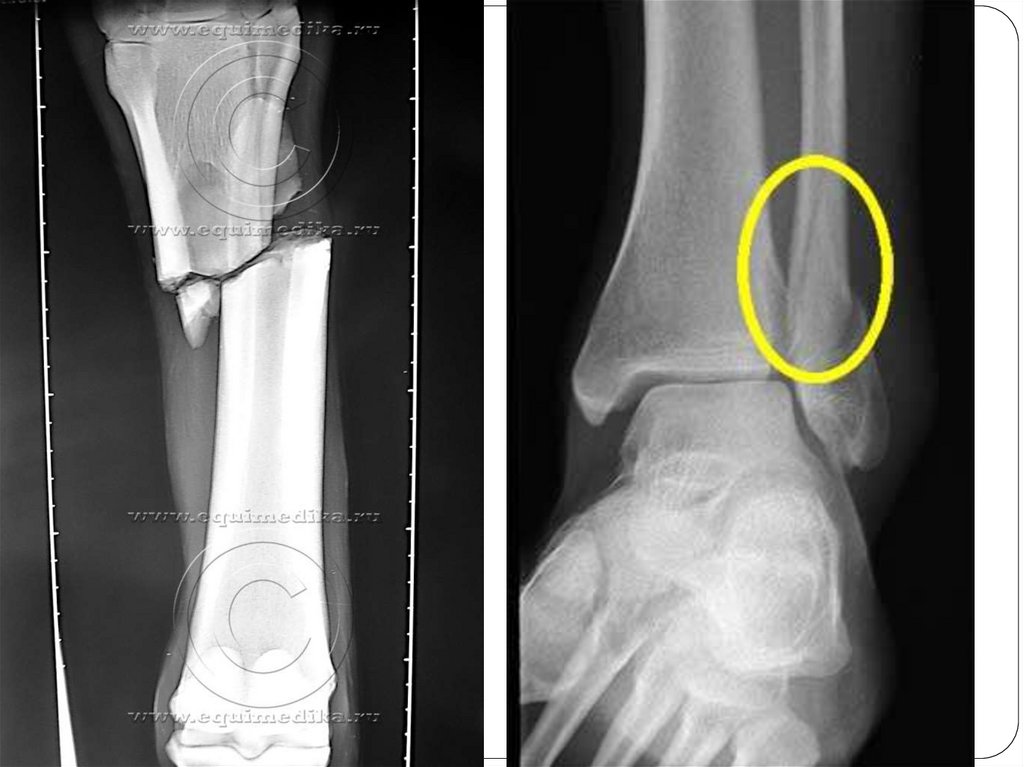

V. По локализации:

Диафизарные – наиболее часто

встречающиеся в клинической практике. В

диагнозе обычно указывают более точное

расположение перелома на протяжении

диафиза – в верхней, средней или нижней

трети.

VI. По линии перелома:

Поперечные – линия перелома располагается

перпендикулярно к оси кости.

Продольные – линия перелома идет вдоль оси

кости.

Косые – линия перелома направлена под углом к

оси кости.

Винтообразные или спиральные – возникают от

скручивания отломков кости по ее оси.

Оскольчатые – с образованием нескольких костных

фрагментов.